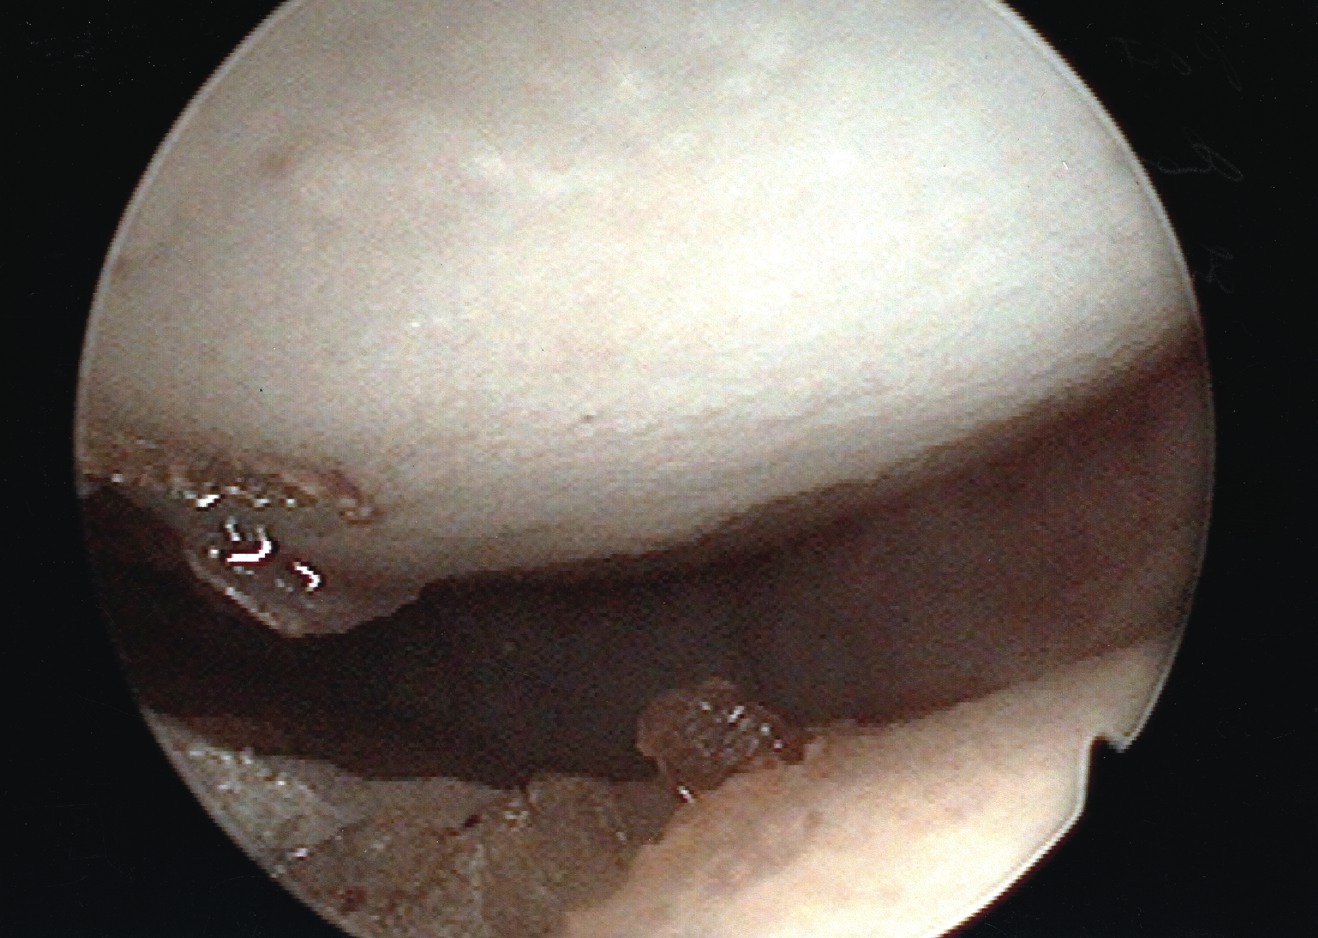

Accordingly, we recently undertook a study to evaluate the technical ease of using this approach to treat patients with plantar plate derangement, metatarsalgia and synovitis of the second metatarsophalangeal joint complex, and to assess early postoperative clinical findings. In regard to the surgical repair, we initially address the metatarsalgia, proceed to repair the plantar plate derangement and finally, using the radiofrequency-based device to ablate the synovitis affected tissue of the second metatarsophalangeal joint complex, we perform the microcapsulotomies of the plantar plate. To treat the plantar plate derangement, one makes an s-shaped incision from the distal third of the second metatarsal shaft and carries the incision to the base of the proximal phalanx. Then you would expose the superior aspect of the head and neck of the metatarsal via sharp dissection. Proceed to open and expose the dorsal aspect of the metatarsophalangeal joint. Then we perform a shortening Weil-type osteotomy of the second metatarsal.9,10 We perform the osteotomy from the dorsal distal aspect of the metatarsal and translate it toward the proximal plantar, just proximal to the plantar condyles and parallel to the plantar aspect of the foot. We adjusted the distal osteotomized capital fragment proximally (3 to 5 mm) to eliminate clinical prominence of the metatarsal head in the plantar position. We proceeded to fixate the osteotomy site with two 0.035 mm guide wires and secured it with either a 2.0 mm or a 2.4 mm compression screw. After decompression of the second metatarsophalangeal joint and internal fixation of the second metatarsal shaft, we applied gentle digital traction to distract and open up the second metatarsophalangeal joint complex. Using a 2.7 mm angled arthroscope, one can evaluate the joint to determine the extent of the synovitis. Following inspection, the surgeon can perform a synovectomy using the Topaz microdebrider device (ArthroCare) as directed by the manufacturer’s instructions. With continued digital traction, we examined the plantar capsular structures and plantar plate. We used the Topaz device to perform the microcapsulotomy procedure in the degenerated plantar plate. The purpose of this step is creating a low-grade inflammatory response necessary for stimulating a healing response in the degenerated tissue. For both ablation procedures, one can use the Topaz device at controller setting 4. For the microcapsulotomy, however, we used the system timer (set at 0.5 seconds) while making each microablation in order to specify a sufficient ablation. We created microablations over the affected tissue region to form a grid-like pattern. Every fourth microablation was slightly deeper in order to ensure adequate penetration of treatment. The affected plantar plate area usually required nine to 12 microablations. After concluding the microablation portion of the procedure, we irrigated the treated area and closed it in standard fashion. We subsequently repaired any associated contributory deformities, such as hallux adductovalgus and/or hammertoe deformity as appropriate. In regard to the radiofrequency-based portion of the procedure, it was slightly more challenging than surgical resection. However, it did offer the benefit of preserving the plantar plate and avoided a plantar incision.